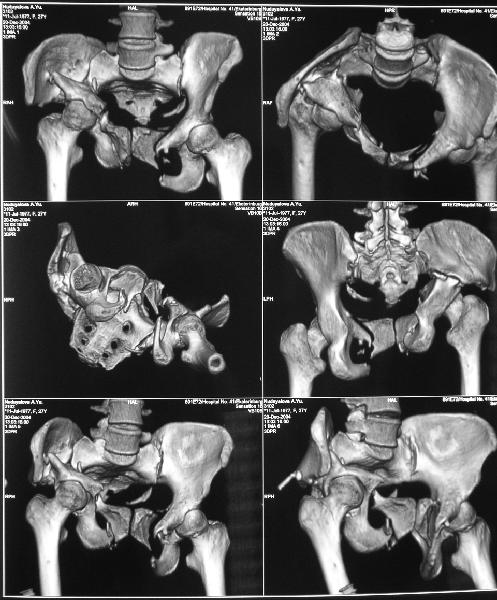

Госпитализирована больная 27 лет. Травма 1.5 года назад, сбита авто. При поступлении в местной больнице наложен фиксационный аппарат-«передняя рама». Через месяц аппарат снят из-за нагноения, разрешена ходьба с костылями. В послеоперационном периоде отмечалось нагноение забрюшинной гематомы. При обрашении к нам 3 мес назад в области промежности имелся свищ, по месту жительства выполнено иссечение свища, был гнойный затек на бедре, откуда получено до литра гноя, больная ходила с костылями.Свищ зажил 1,5 мес назад При поступлении сейчас укорочение до 5 см, ходит без дополнительной опоры, имеется выраженная хромота.Какой, по вашему, может быть оптимальная тактика оперативного лечения? Ограничиться низведением вертлужной впадины (каким доступом?), выполнить полную реконструкцию передних и задних отделов, одномоментно или поэтапно? Заранее благодарен.

Should you deem her fit for surgery, the 3-D CT alone is insufficient for planning preoperatively. We can¹t see the healing response, soft tissue envelope, the right SI injury, nor the left SI joint problem well enough on the 3-D CT alone.

In other hand, I would like to see the primary X rays, because with 3D-CT alone I cannot classify that fracture into Letournel's classification. Maybe it is a posterior hemitransverse with anterior column fracture.

По просьбам коллег отправляем снимки таза: прямая, inlet, outlet, 2 дополнительные компьютерные томограммы.

О виртуозности владения аппаратным лечением, неоднократно доказанным на ваших материалах, со стороны русских коллег, все таки голосую за многоэтапность лечения, конечно после нормального обследования, снимки таза: прямой, инлет, оутлет и КТ, а представленная 3D, не представляю

во сколько обошлась больной, кроме красивого рисунка, не дает нужную информацию для специалиста. Обычные КТ срезы дают информацию о

сращении, от которого и зависит тактика лечения.